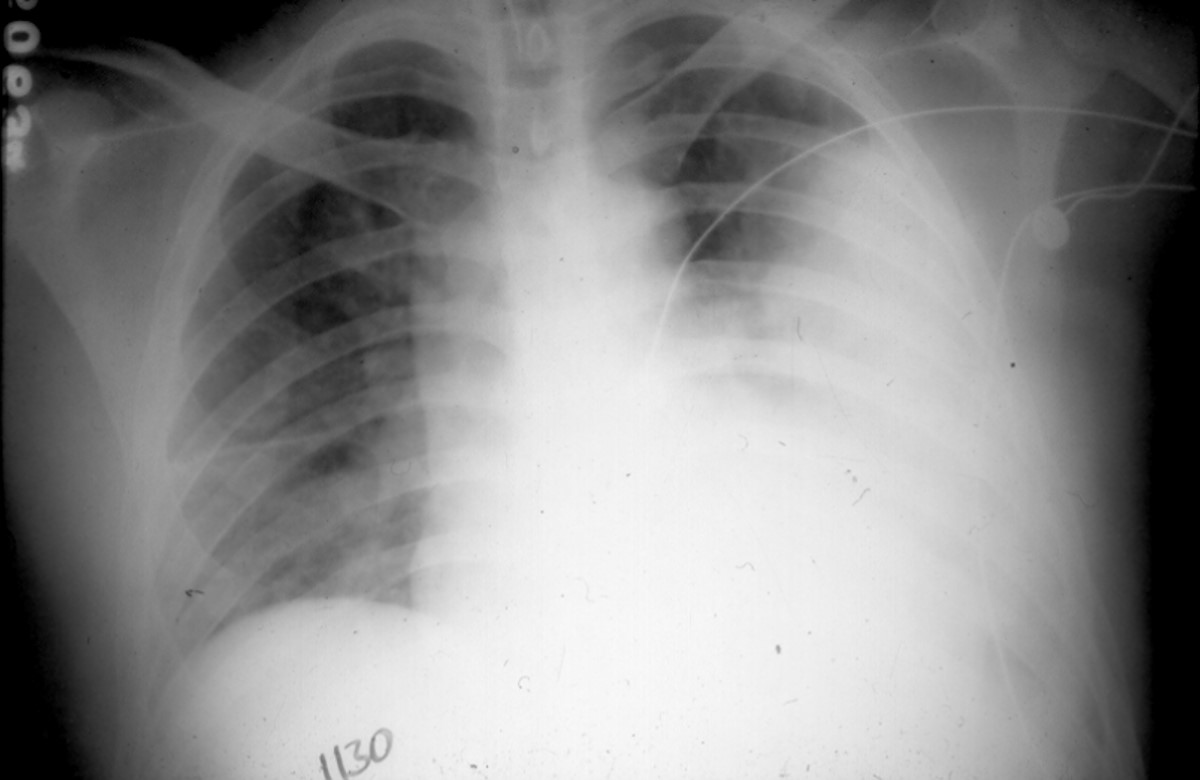

Panel A. A portable chest x-ray obtained on admission of the patient to your care.

The x-ray shows a consolidating pneumonia of the left lower lobe and a right-sided

patchy "atypical" pneumonia and median fissure effusion.